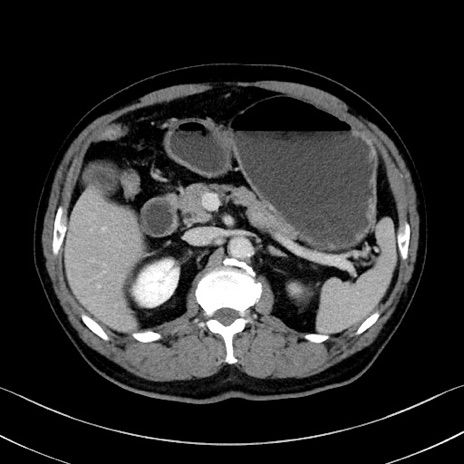

症例35(横断像)

【症例】70歳代 男性

【主訴】腹部膨満、嘔吐

【現病歴】昨日より腹部膨満感出現。本日増悪し、仙痛出現。嘔吐あり、受診。

【既往歴】糖尿病、胆摘後

【身体所見】BP 149/80mmHg、HR 74/min、BT 35.9℃、腹部:膨満、軟、圧痛なし。腸雑音減弱あり。上腹部正中切開瘢痕あり。

【データ】WBC 13500、CRP 1.72